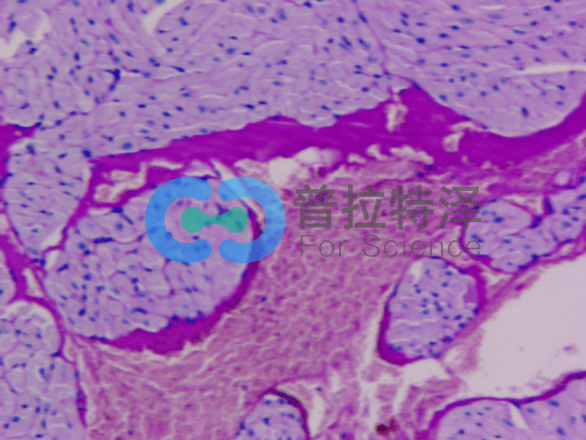

②腎臟疾病診斷

PAS染色在腎臟疾病診斷中同樣發(fā)揮著重要作用。對(duì)于腎小球腎炎、腎小管間質(zhì)性腎炎等疾病,PAS染色可以清晰地顯示腎小球基底膜、腎小管及間質(zhì)等結(jié)構(gòu)的變化,有助于醫(yī)生做出準(zhǔn)確的診斷。